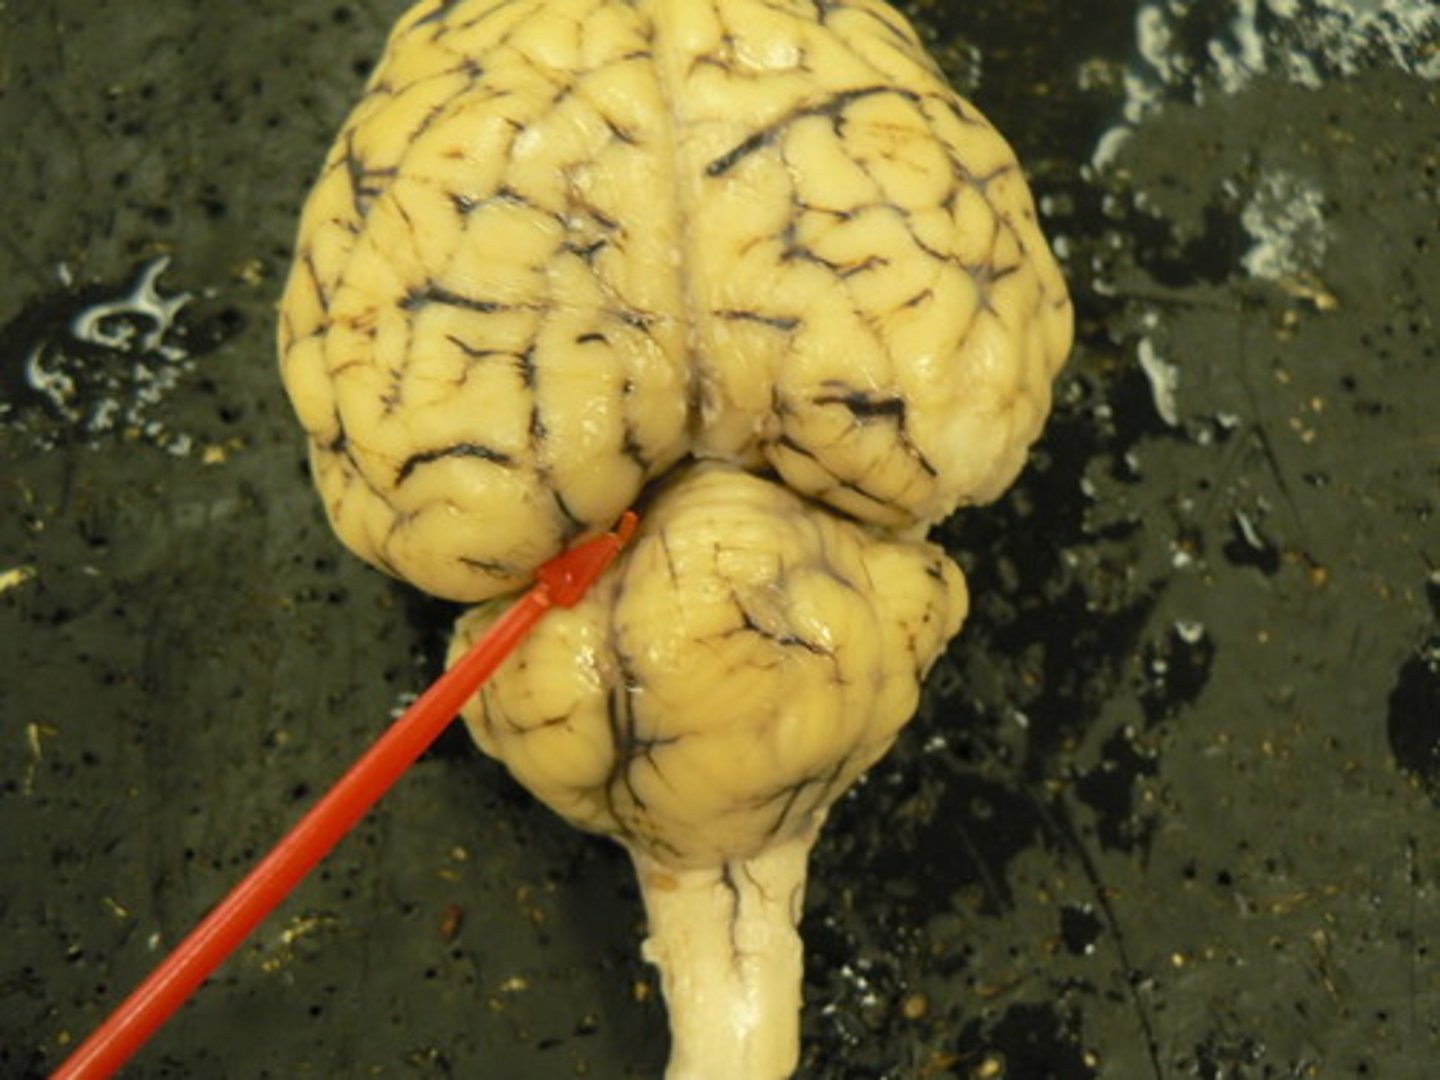

Cerebrum

Large, deeply wrinkled region of the brain responsible for conscious experience including perception, emotion, thought, and planning (#1)

Cerebellum

Controls movement, balance, and muscle coordination (#2)

Spinal cord

Bundle of nerve fibers inside the spine that connects the brain to the sensory and motor parts of the body (#3)